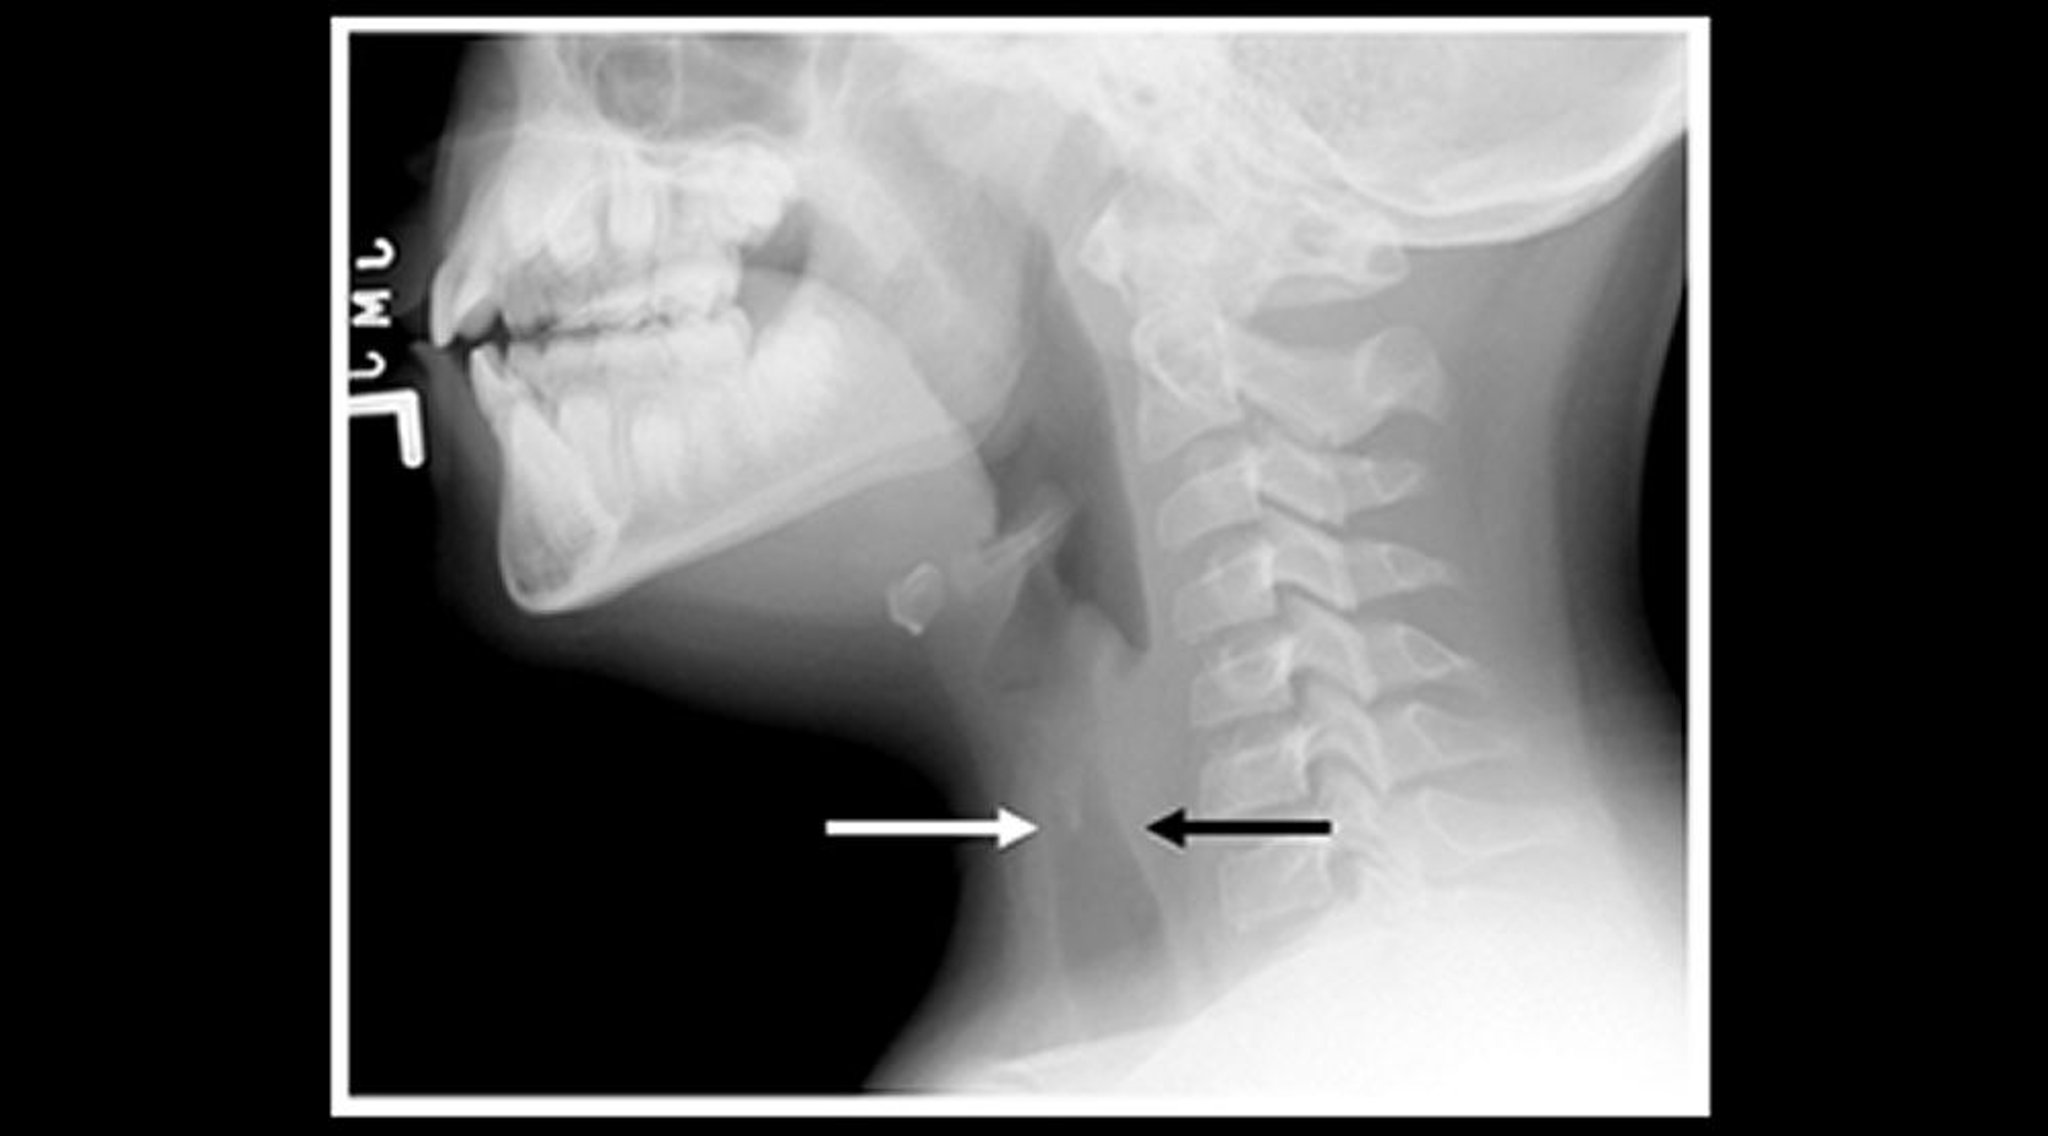

Radiografía de un niño con laringotraqueobronquitis espasmódica (crup) (cista sagital)

Radiografía de partes blandas del cuello de un niño con crup que muestra estrechamiento de la sombra aérea traqueal subglótica (flechas) y dilatación de los espacios aéreos faríngeos.